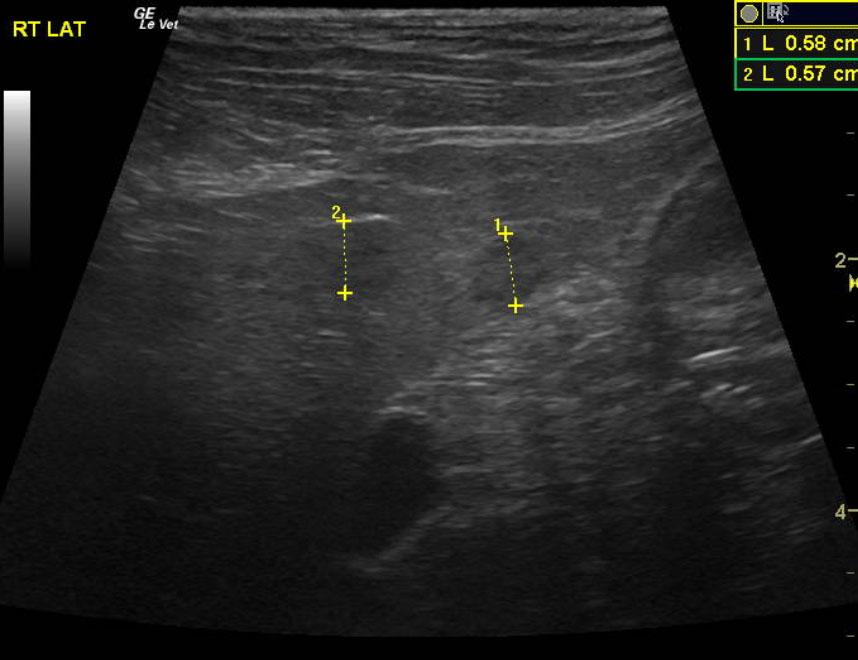

A 15-year-old MN DMH cat was presented for chronic diarrhea, hyperthyroid, dehydration, otitis externa, and periodontal disease. The CBC was markedly normal with blood chemistry revealing an elevated ALT (154,) elevated SAP (109,) hyperT4 (>10,). An IDEXX feline diarrhea panel was negative for virus, parasites, & bacteria.